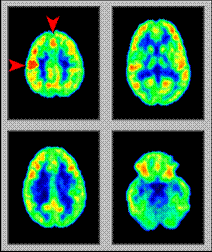

The Resting Brain

• PET Scans Show Brain Function

• Four Different Slices of the Same Brain

• Mapping of Cerebral Function

• Resting Brain Shows No “hotspots”

Visual Activity

• Subject exposed to visual stimulation consisting of both pattern and color.

• Increased activity in the stimulated brain PET image (arrowhead).

• Region of increased activity corresponds to the primary visual cortex.

Thinking Activity

• Region of increased activity corresponds to the frontal cortex.

Memory Activity

• Subject required to remember an image for later recall.

• Increased activity in the stimulated brain PET image (arrowhead) is the hippocampal formation.

• Region of the brain implicated in learning and memory.

Motor or Kinesthetic Activity

• Motor stimulation of the brain

• Subject to hop up and down on his right foot.

• Motor task of a movement of the right foot caused:

• Cortical metabolic activation of the left motor strip (horizontal arrowhead)

• Caused supplementary motor cortex (vertical arrow, top).